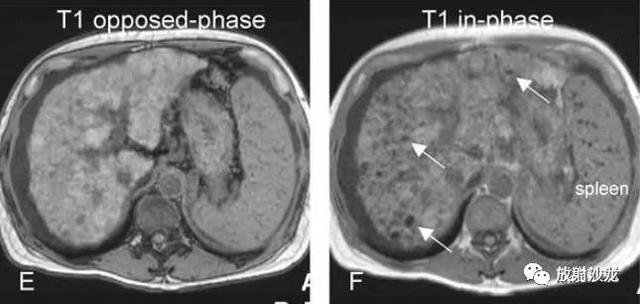

各基本序列信号特征

T2 fatsat:未见病灶显示;

同反相位:反相位呈低信号,提示局灶性脂肪浸润;

ART:动脉期,由于脂肪抑制呈低信号,无明显强化;

DEL:延迟期,仍呈低信号。

DN-HCC转变,MRI表现

A~D:影像表现如上所述。12个月后复查:

E:T2压脂未见明确病灶;

F:同反相位示病灶体积增大,反相位呈低信号;

G:动脉期,结节有强化;

H:延迟期,结节内造影剂廓清,提示其为DN并局灶性HCC。